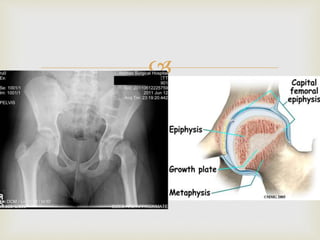

 Displacement of the capital femoral epiphysis from

the femoral neck through the physeal plate

Slipped capital femoral epiphysis (SCFE)   Displacement of the capital femoral epiphysis from the femoral neck through the physeal plate  Boys affected more than girls  Occur during puberty usually 14-15 years old  Risk factors:  Obesity  Very tall  Endocrine problems :hypothyroidism, panhypopituitarism, hypogonadism,, growth hormone abnormalities